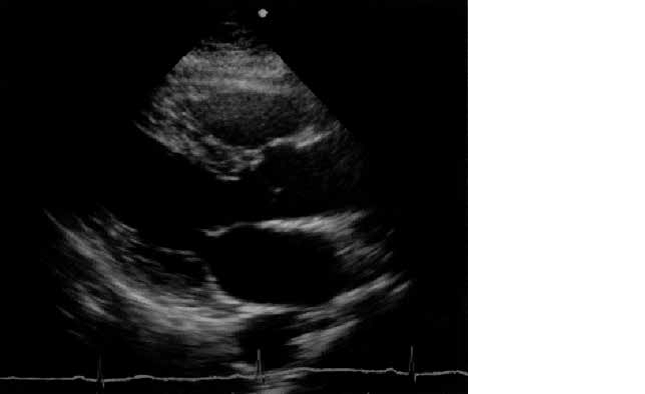

傍胸骨からの心エコー図を示す。

見られないのはどれか。

• 1. 右 房

• 2. 右 室

• 3. 左 房

• 4. 左 室

• 5. 大動脈